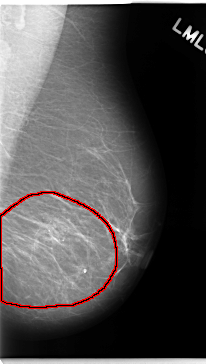

C_0138_1.LEFT_CC

LEFT_CC LINES 4736 PIXELS_PER_LINE 2640 BITS_PER_PIXEL 12 RESOLUTION 50 OVERLAY

FILE: C_0138_1.LEFT_CC.OVERLAY

TOTAL_ABNORMALITIES 1

ABNORMALITY 1

LESION_TYPE CALCIFICATION TYPE AMORPHOUS DISTRIBUTION REGIONAL

ASSESSMENT 5

SUBTLETY 3

PATHOLOGY MALIGNANT

TOTAL_OUTLINES 1

BOUNDARY